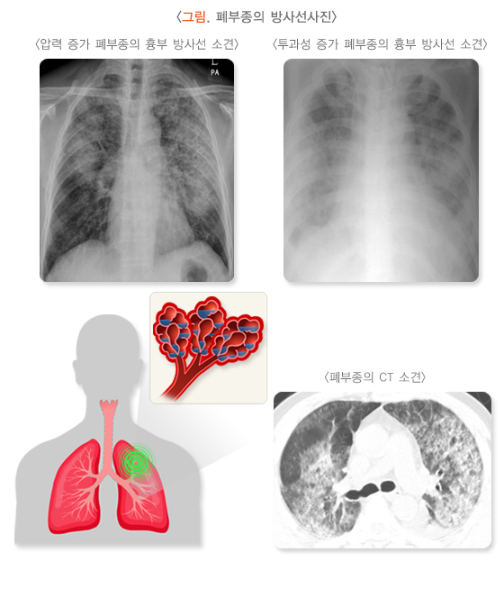

3. 영상검사 (Imaging Tests)

영상검사는 폐경화증의 진단과 병기 결정에 매우 중요한 역할을 합니다.

- 흉부 X선 (Chest X-ray): 흉부 X선은 폐경화증을 의심할 수 있는 첫 번째 검사입니다. 흉부 X-ray에서 폐의 확장과 섬유화가 나타날 수 있습니다. 폐경화증이 진행됨에 따라 폐 조직의 흉터나 염증이 보일 수 있습니다. 그러나 X선은 초기 섬유화를 완전히 확인하기 어렵기 때문에, 추가적인 검사가 필요할 수 있습니다.

- 고해상도 컴퓨터단층촬영 (HRCT, High-Resolution CT): HRCT는 폐경화증을 진단하는 데 매우 중요한 검사입니다. HRCT는 폐의 세부 구조를 선명하게 보여주며, 폐의 섬유화 정도, 폐렴의 여부, 기타 이상을 확인하는 데 유용합니다. HRCT에서 기저 섬유화, 미세한 흉터(interstitial fibrosis), 기타 폐의 비정상적인 변형을 확인할 수 있습니다. 이는 폐경화증의 심각도를 평가하는 데 중요한 정보를 제공합니다.